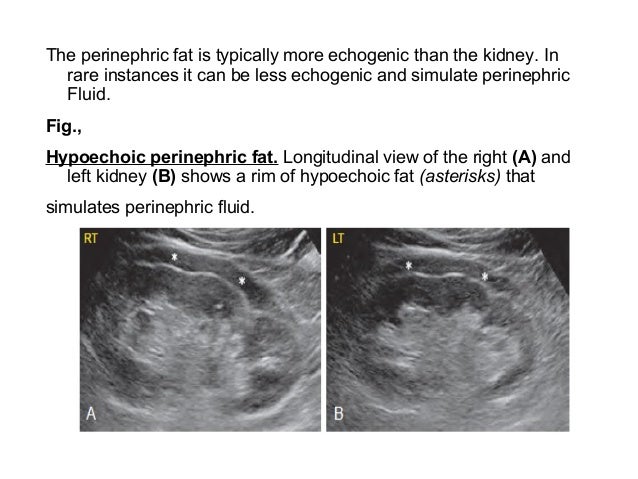

Hydronephrosis Normal Vs Abnormal Kidney Ultrasound. Classification is based on the ectopic kidney s anatomic position. In this context it is important to note that obstructive nephropathy may be missed due to false negative findings in the setting of acute or partial obstruction volume depletion and retroperitoneal fibrosis.

Classification is based on the ectopic kidney s anatomic position. This is called crossed ectopia. Ultrasound images as well as illustrations demonstrating these grades of hydronephrosis are shown in figure 1.